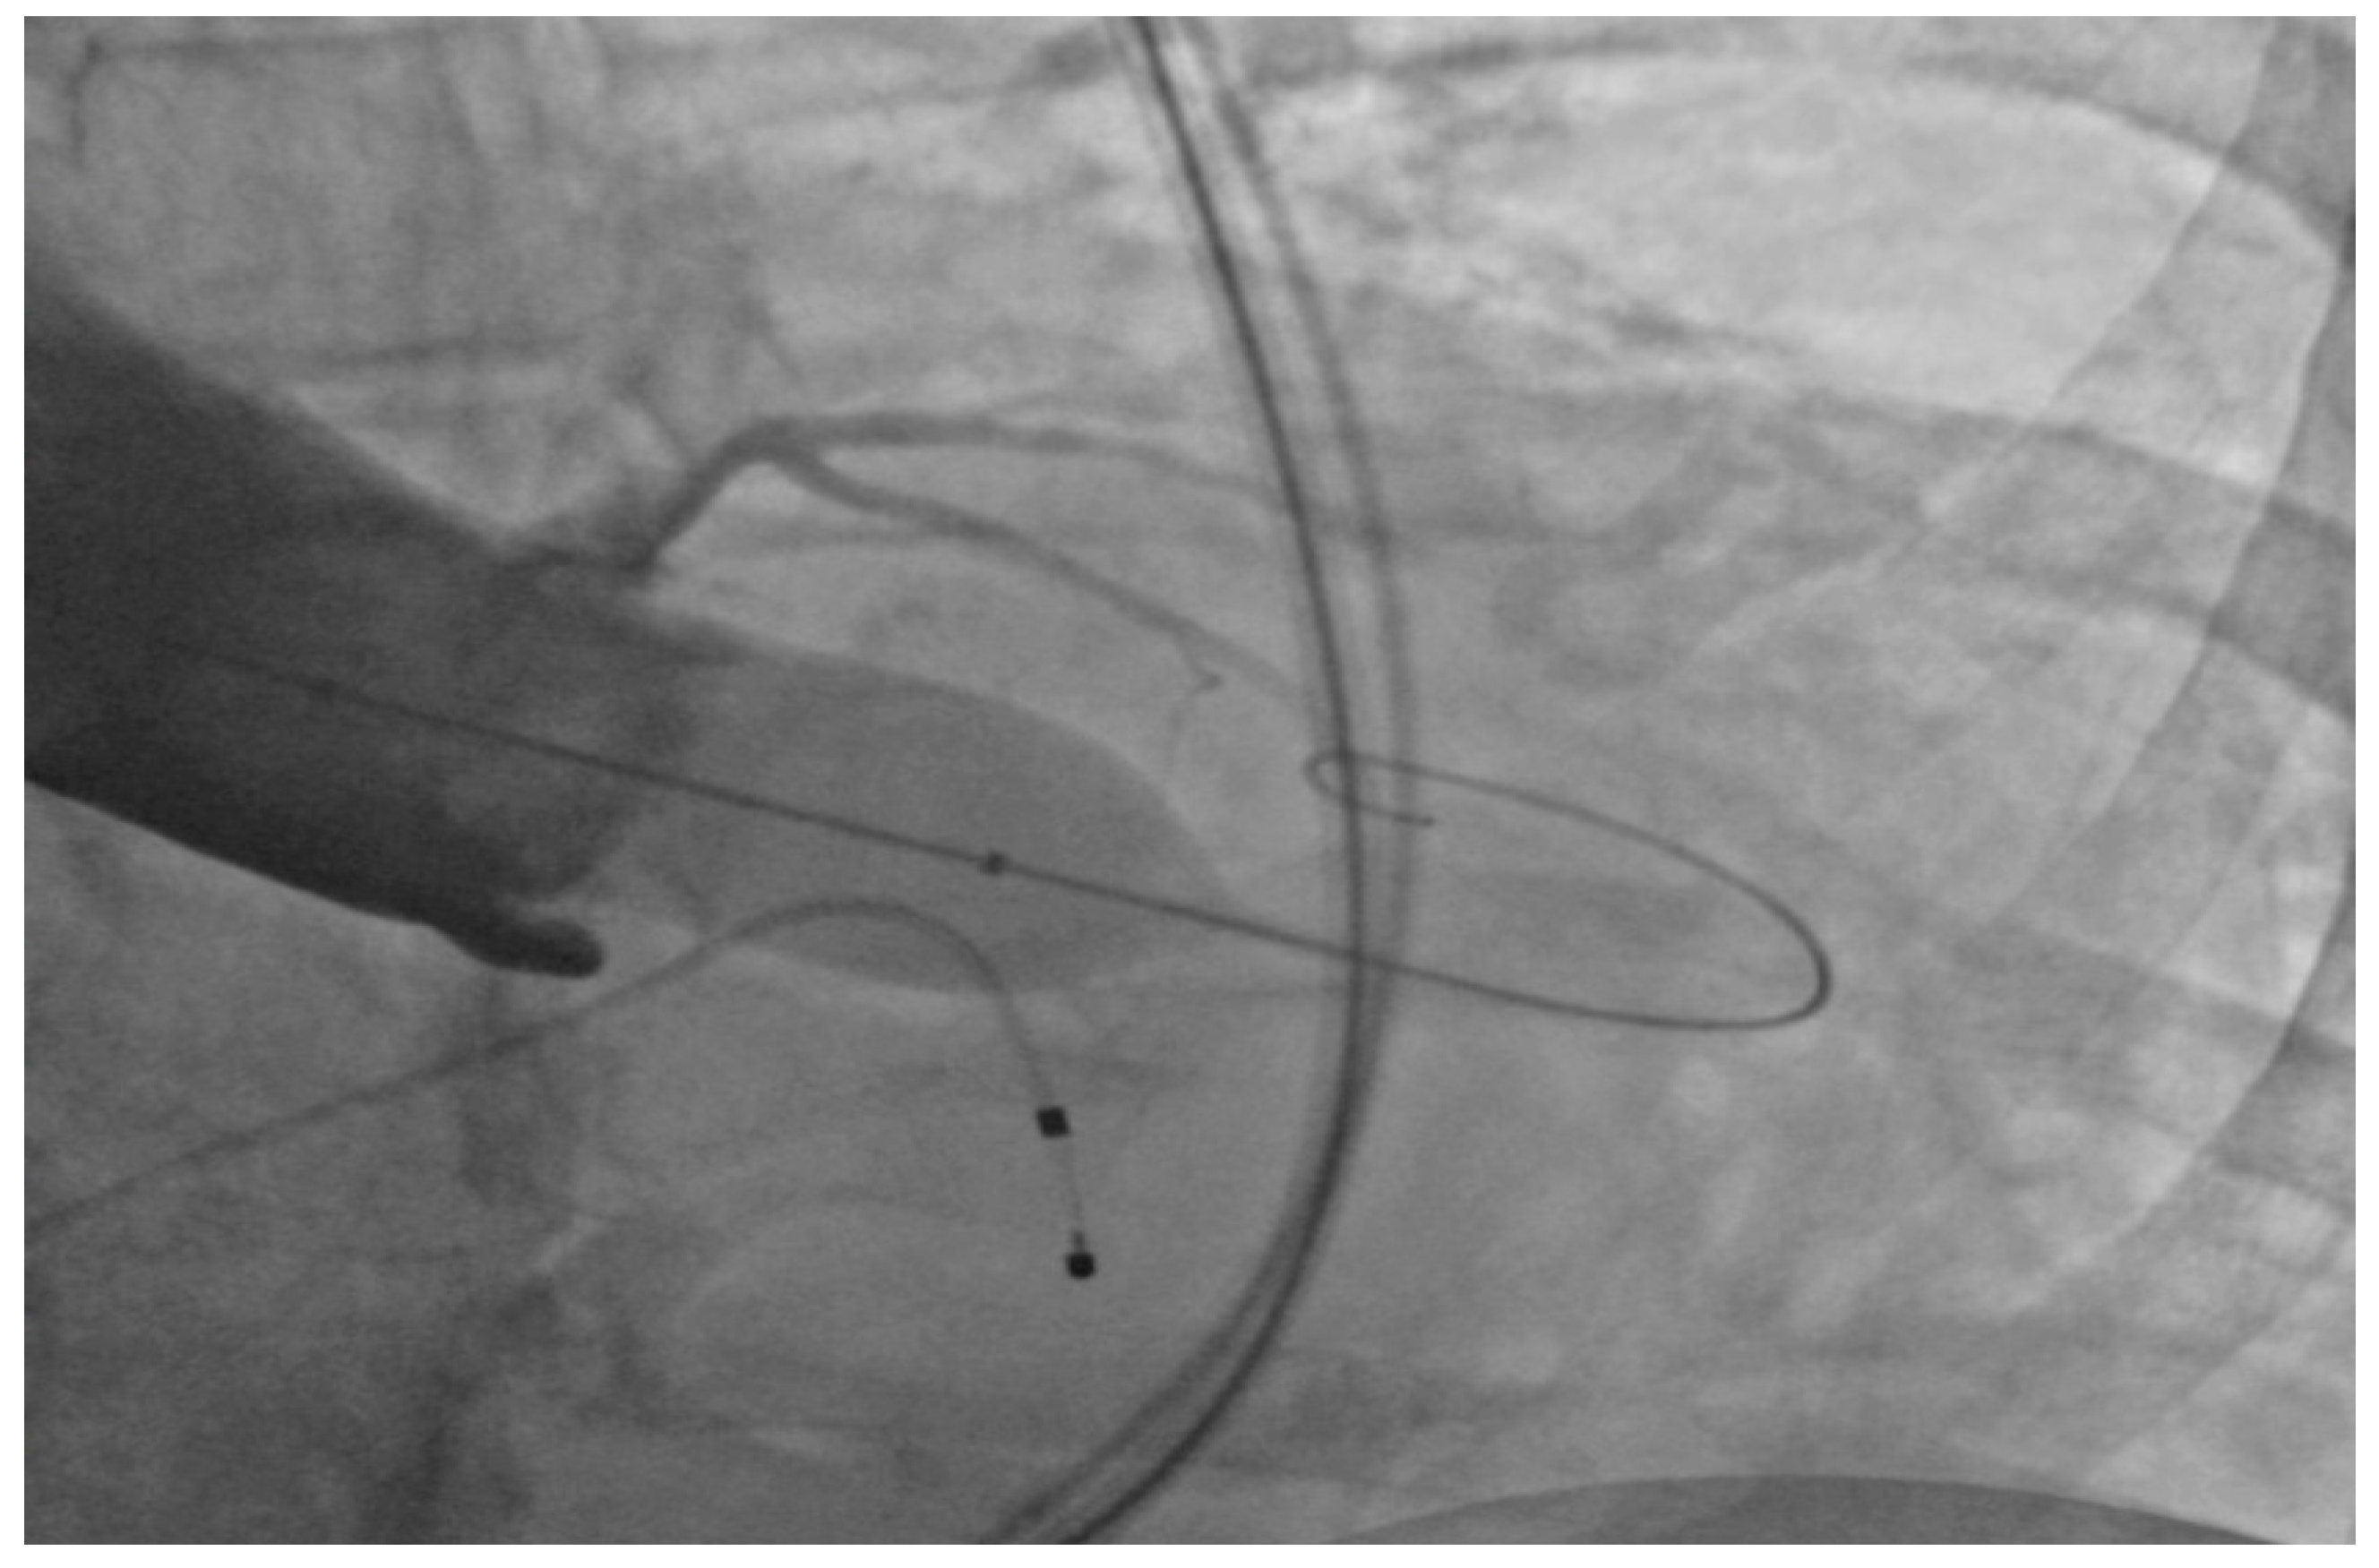

Under general anesthesia, the right and left femoral arteries were each accessed with 6-french sheaths. A temporary pacemaker was placed in the right ventricle through an 8-french sheath in the right femoral vein. Balloon valvuloplasty was performed by advancing a balloon via the right femoral artery sheath, and during rapid ventricular pacing at 160 beats per minute, inflating it across the aortic valve to clear the stenosis and to deploy the 26-mm SAPIEN S3 bioprosthetic aortic valve (Figure 1), which expanded within the native aortic valve (Figure 2). The purpose of rapid ventricular pacing during TAVI is to reduce cardiac output, which facilitates balloon inflation across the valve and placement of the bioprosthetic aortic valve. The mean valvular gradient after TAVI decreased to 1.9 mm Hg (normal is <5 mm Hg). There were no intraoperative complications. The patient was extubated and transferred to the coronary care unit with the temporary transvenous pacemaker, which was removed two days later.

Figure 1.

Balloon inflation across the aortic valve.